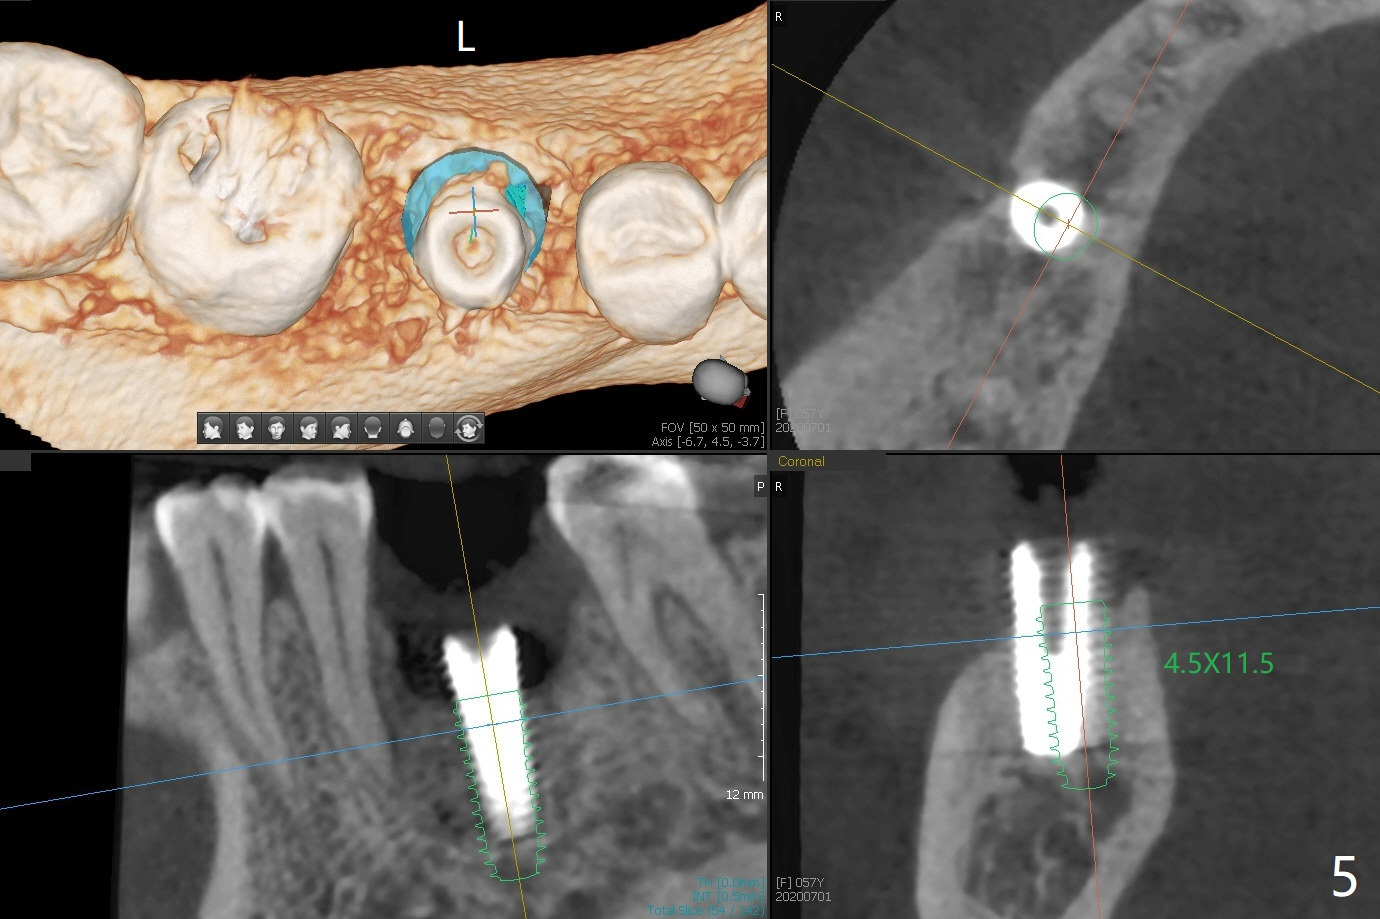

When the woman with periimplantitis at #30 returns to clinic, the abutment is found to be fractured (Fig.1 *) and difficult to remove. After implant removal with trephine burs, osteotomy is initiated lingual (Fig.2). A smaller and shorter implant (4.5x11.5 vs. 5.0x13 mm previously) is placed deeper (Fig.3) so that there is space for sticky bone buccal and coronal (Fig.4 *, 5 (postop reanalysis of preop CT)). After placement of 2 pieces of PRF membranes, the wound is closed with 4/0 PGA. The buccal flap is perforated due to periimplantitis and surgical manipulation. Periodontal dressing is applied.